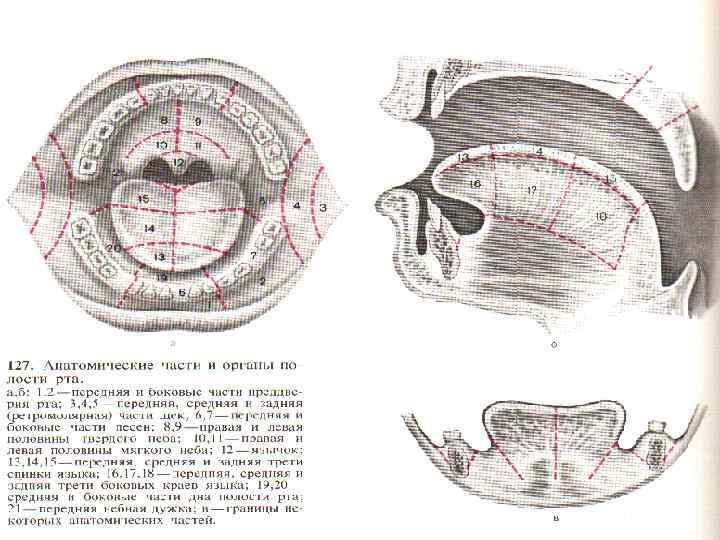

Общая характеристика опухолей полости рта Слизистая полости рта и подлежащие ткани представляют особую анатомическую сложность, обусловливающую специфику клинического течения и лечения развивающихся здесь опухолей. Это преимущественно различные виды плоскоклеточного рака – 90 -95%. В клинической практике приходится встречаться с многочисленными видами новообразований.

Общая характеристика опухолей полости рта Слизистая полости рта и подлежащие ткани представляют особую анатомическую сложность, обусловливающую специфику клинического течения и лечения развивающихся здесь опухолей. Это преимущественно различные виды плоскоклеточного рака – 90 -95%. В клинической практике приходится встречаться с многочисленными видами новообразований.